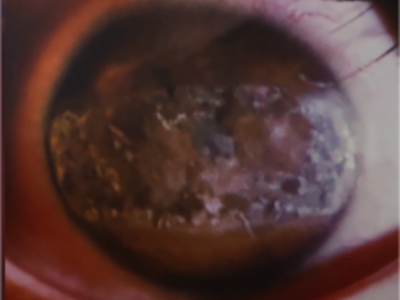

带状角膜病变眼球有混浊的白色斑块图

带状角膜病变发生于眼球边缘部时,会出现白色的混浊斑,边界清晰,主要由钙质沉积造成。此时应及时就医,避免症状加重后导致视力下降。